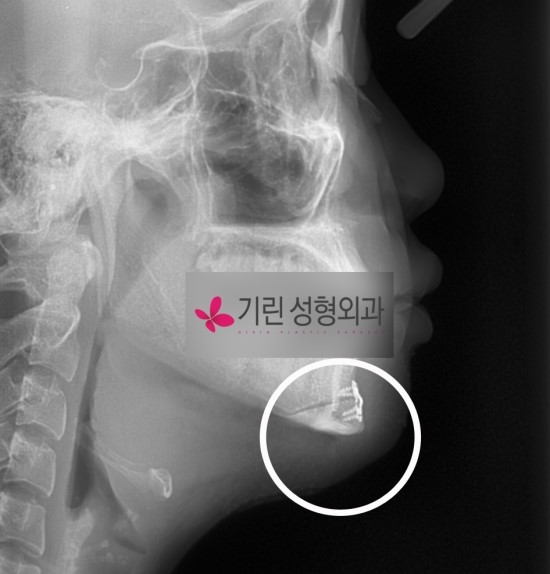

[안면윤곽수술 후 : 앞턱줄임술, 사각턱수술]

샌드위치절골로 길이를 줄일 수 있는데 이 때 전후진의 비율을 정확히 맞춰 고정을 하지 않으면 어색해보입니다. 정확한 전후진범위의 파악과 적절한 길이줄임이 윤곽수술에서 중요한 수술포인트입니다. 아래는 동인인의 안면윤곽수술 전후 시티사진입니다.